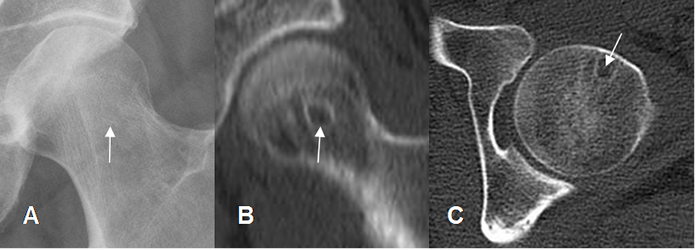

Fig 31 B. Herniación sinovial.

A: Rx AP, B: TAC reconstrucción coronal y C: TAC axial. Imagen redondeada y de bordes escleróticos, localizada en la parte anterior de la cabeza femoral, que corresponde a herniación sinovial.